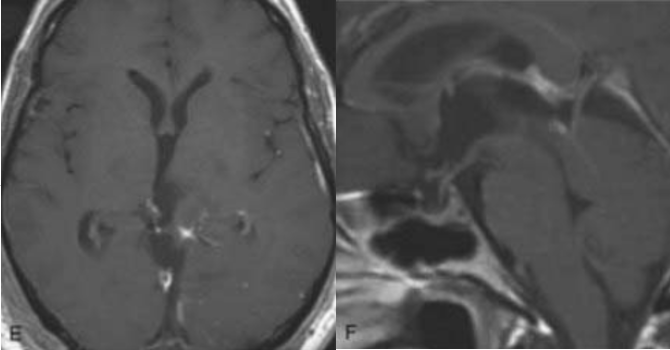

3岁患儿因典型的Parinaud综合征就诊,影像学证实为顶盖区神经胶质瘤延伸至第三脑室后部。若不及时干预,这种眼球运动障碍很可能进展为永久性残疾。手术团队采用小脑上幕下入路,在有限的解剖空间内精细操作,最终实现肿瘤全切除。令人欣慰的是,术后数月内患儿的眼球运动功能获得显著改善。

术前MRI

术后MRI